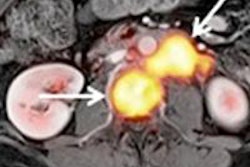

Whole-body FDG-PET/MRI exam of a 1-year-old girl with metastatic teratoma. Combined PET/MRI enables simultaneous acquisition of whole-body MRI (A) and PET (B) as well as local MRI (C.I). MRI shows a paravertebral metastasis (C.I, red arrow), which is metabolically active on FDG-PET (C.II, PET/MRI fusion image).

Whole-body FDG-PET/MRI exam of a 1-year-old girl with metastatic teratoma. Combined PET/MRI enables simultaneous acquisition of whole-body MRI (A) and PET (B) as well as local MRI (C.I). MRI shows a paravertebral metastasis (C.I, red arrow), which is metabolically active on FDG-PET (C.II, PET/MRI fusion image).The PET/CT results suggested an additional MRI scan for local staging and therapy planning for four patients, but the recommendation proved unnecessary except in one case.

"This additional examination [based on PET/CT] became unnecessary after PET/MRI, where local imaging was performed together with whole-body staging in one single examination," the authors wrote. "In one patient, the detection of a suspicious morphological MR correlate for focal tracer accumulation initiated close follow-up imaging and extended treatment."